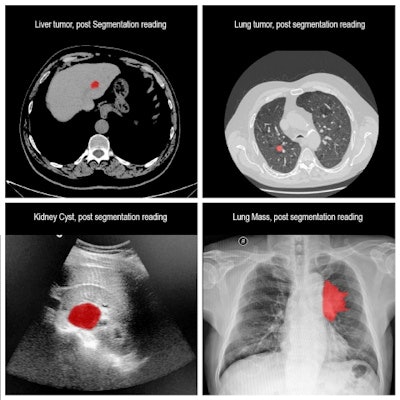

RSIP's AI-based tool can provide multimodality image segmentation and measurements. Images courtesy of RSIP Vision.The tool is suitable for a wide range of applications, including, for example, providing one-click segmentation of lesions in multiple organs such as the lungs and the liver, RSIP Vision said. It's available now to medical device manufacturers worldwide, according to the firm.